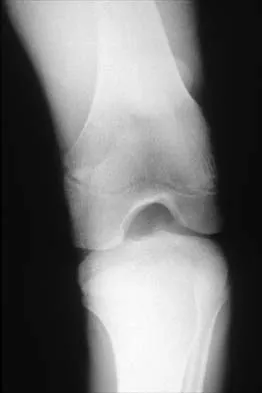

Question 639High Yield

A 12-year-old boy reports knee discomfort after prolonged strenuous activities. He denies knee swelling or catching and has no pain with activities of daily living. A radiograph is shown in Figure 4. Prognosis for the pathology shown is most influenced by

Explanation

While many factors play a role in the outcome of osteochondritis dissecans, ample evidence has shown that the prognosis is most influenced by the growth status of the plates. If the growth plates are open, the chance of a successful outcome is significantly greater than if they are closed. Federico DJ, Lynch JK, Jokl P: Osteochondritis dissecans of the knee: A historical review of etiology and treatment. Arthroscopy 1990;6:190-197.